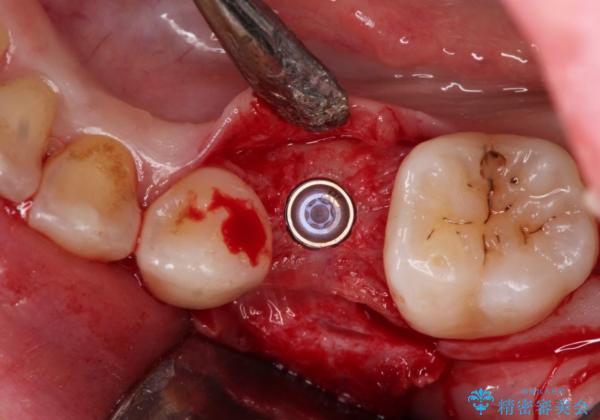

小臼歯のインプラント

- 小臼歯が先天性欠損していたため、インプラントにて補綴しています。

当院ではストローマンインプラントを導入しています。